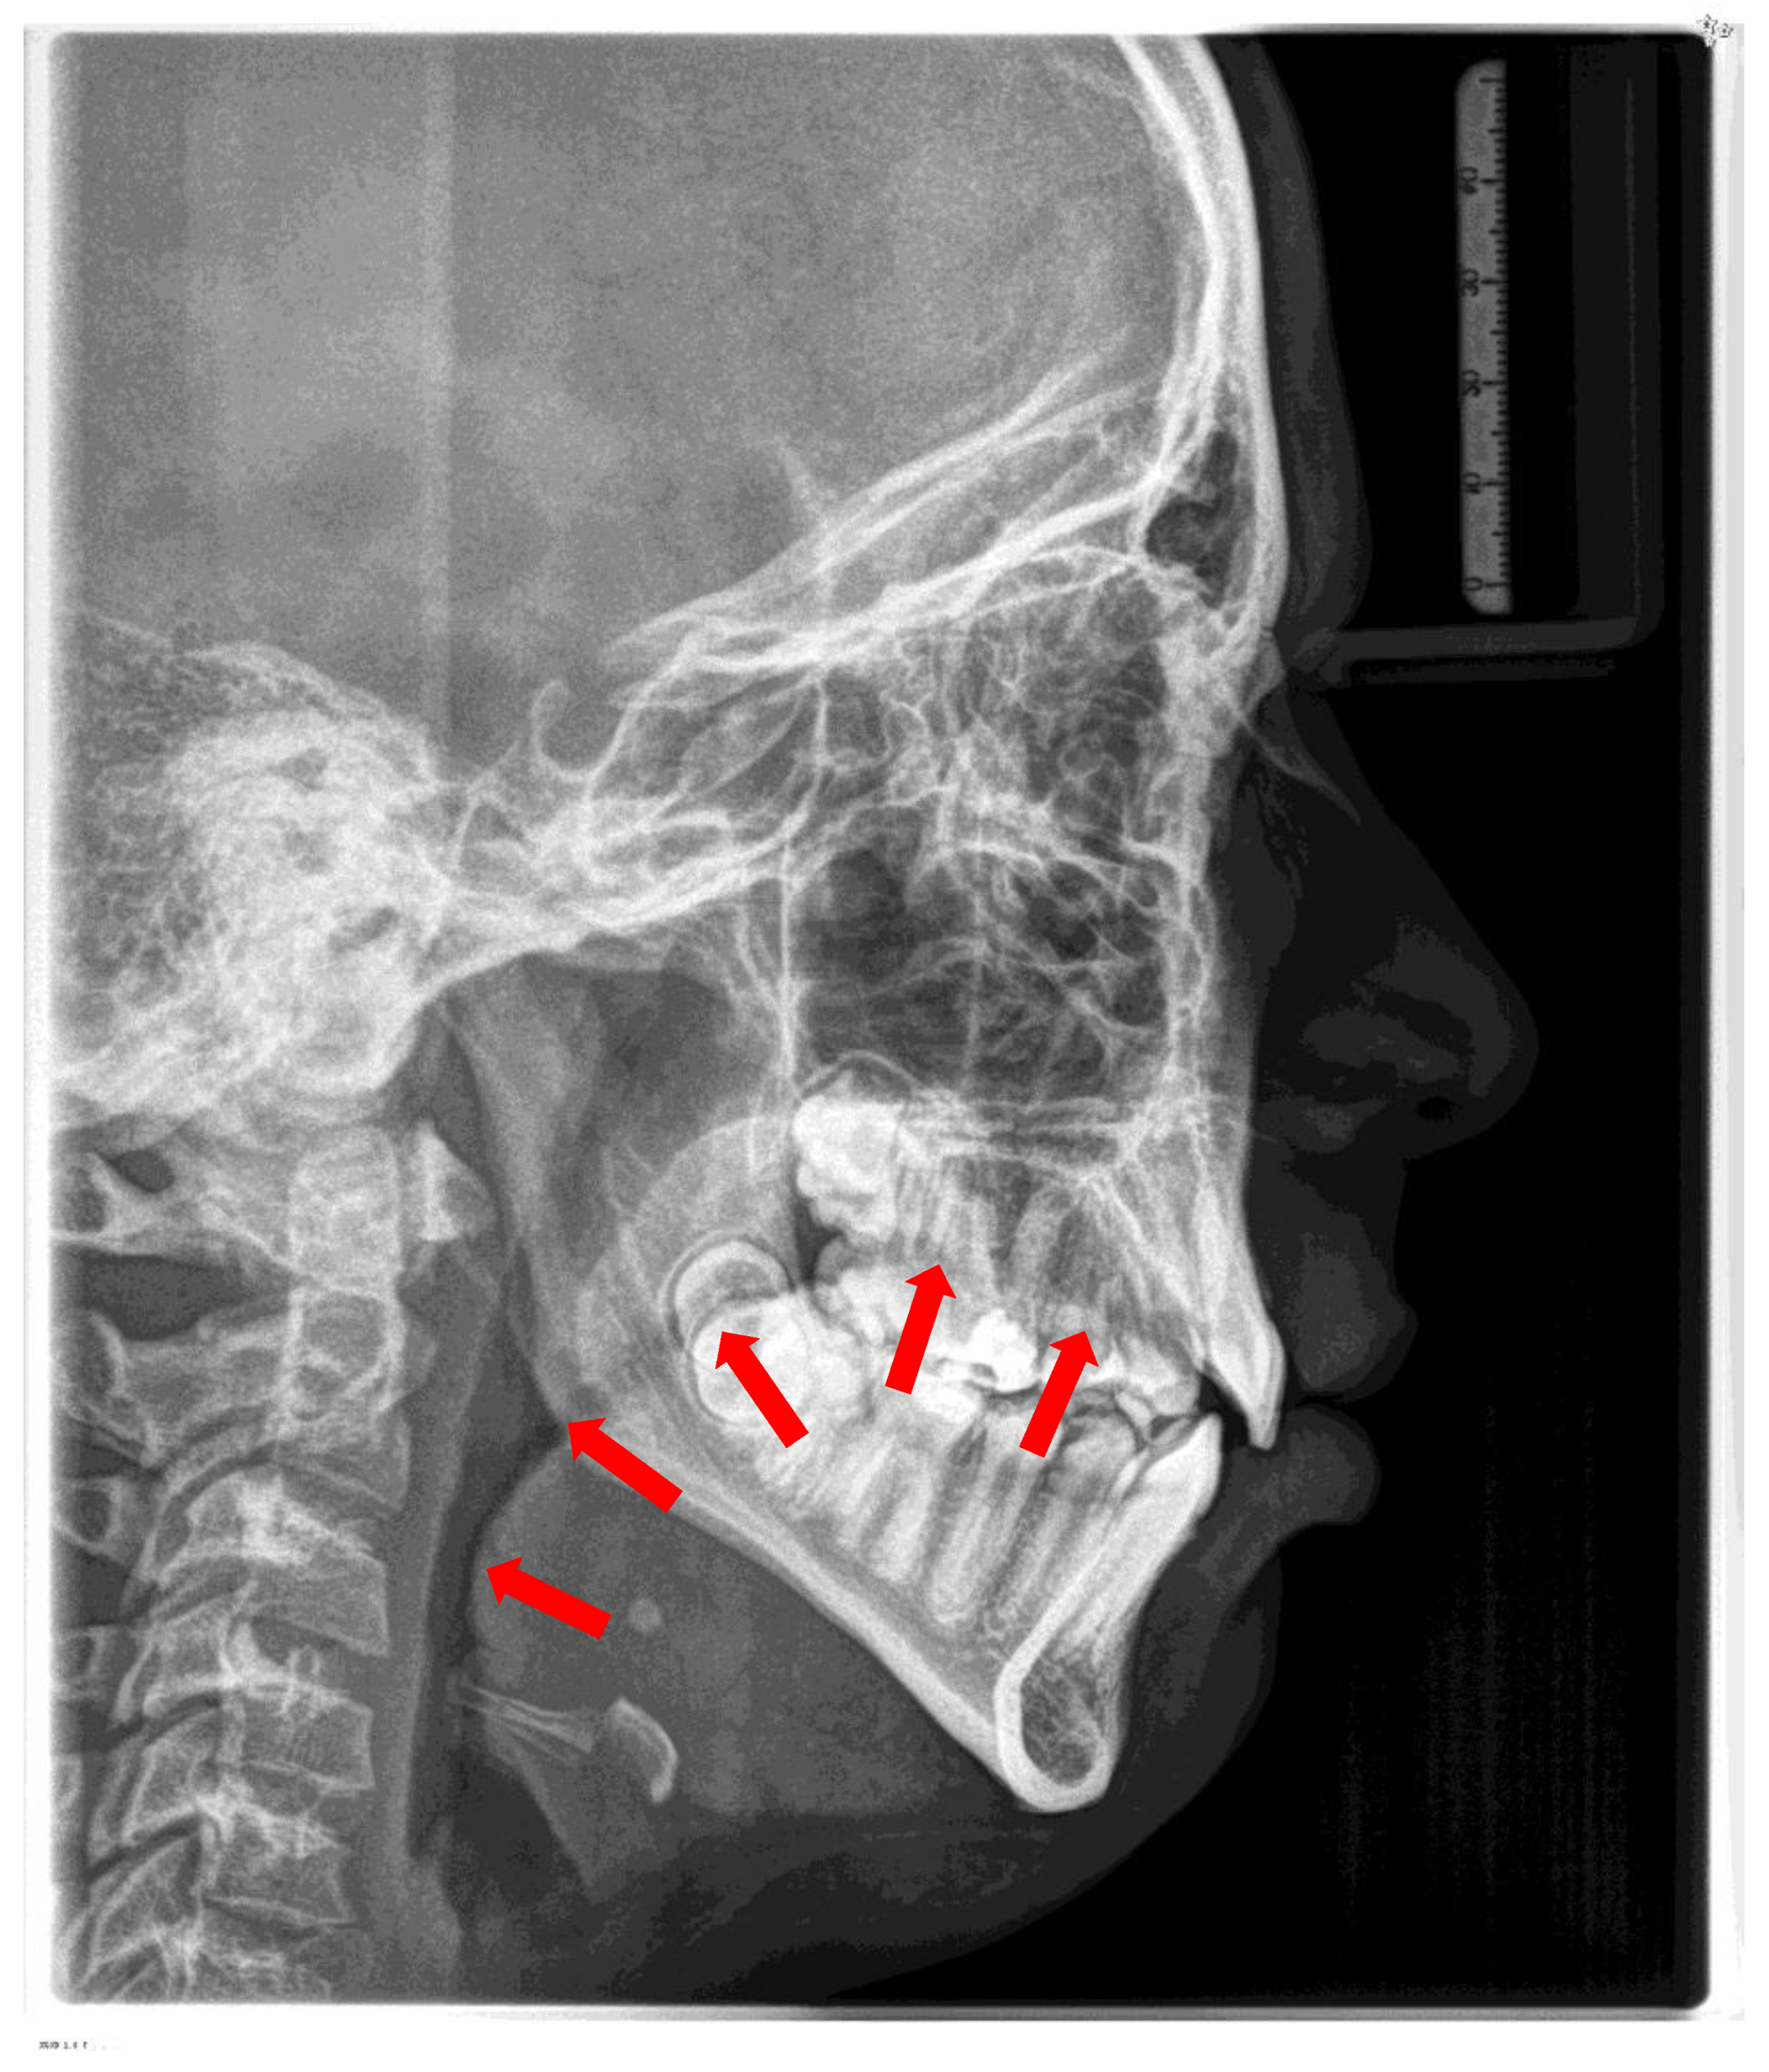

8.9. Mandibular Advancement

A retrognathic mandible induces retrodisplacement of the tongue, thereby reducing the upper airway volume. Orthopedic mandibular advancement was first introduced by Dr. Kingley with the “bite-jumping” appliance in 1879 [129]. This type of appliance aims to correct skeletal mandibular retrognathia. It redirects mandibular growth into a more forward and downward position, either passively or actively, while being worn either fixed or removably (for approximately 15 hours). There are many functional Class II appliances, such as the classical activator and its modifications, the Fraenkel II appliance, the Herbst appliance, the Bionator, the Twin Block, and the bite-jumping appliance (VDP-Sander II appliance). In addition, some can be combined with maxillary expansion (Herbst-RME) appliances. All devices have in common that they bring the lower jaw into the desired therapeutic position. They are worn until the orthopedic effect is achieved. (Figure 15)

Dental and bony changes associated with the use of functional appliances in growing patients are well-documented [130,131]. When devices are worn during growth, mandibular length increases (long-term effect). Expected advancement will be from half cusp to full cusp. The advancement period during treatment typically lasts 6 to 9 months.